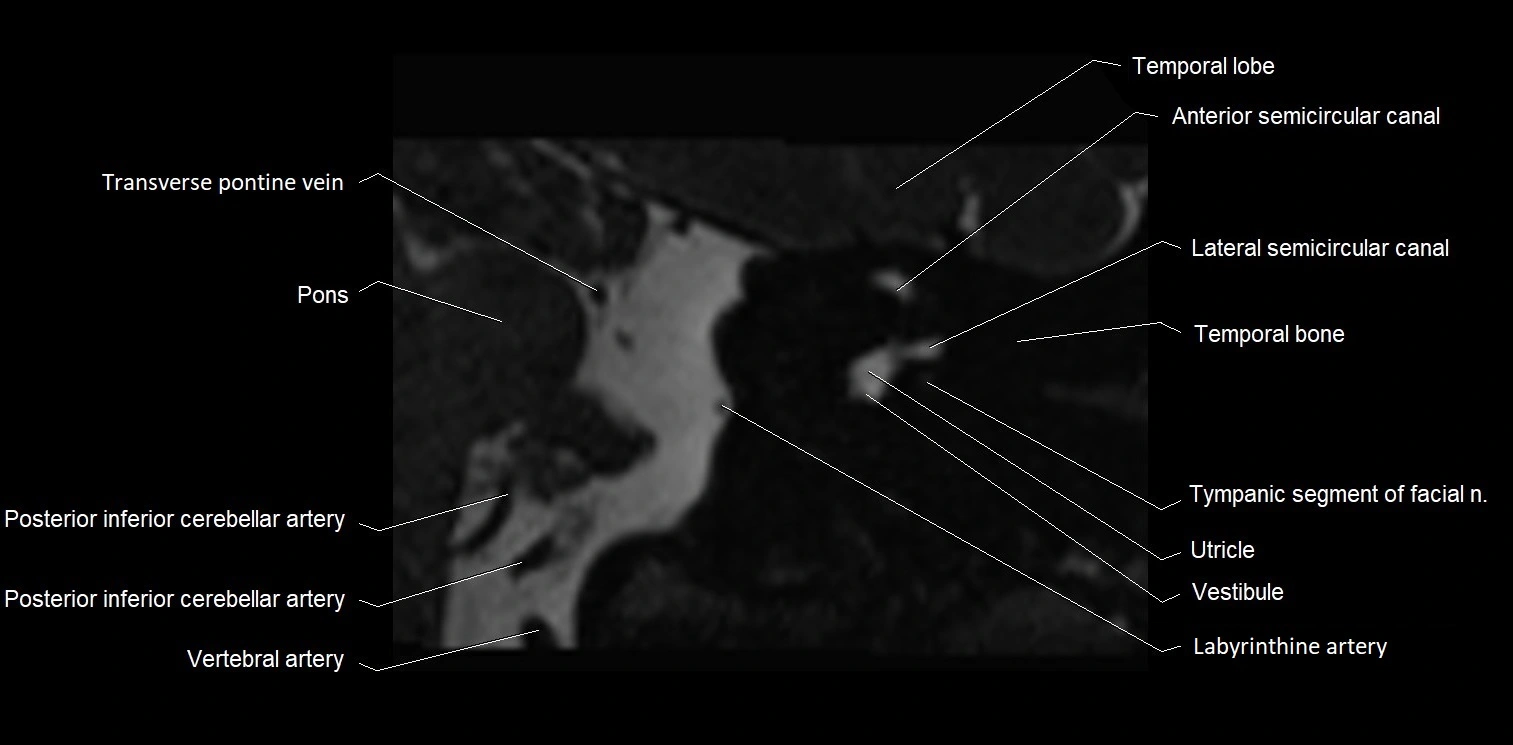

MRI Appearance

• The abducens nerve is a small, thin, linear structure

• Best visualized on high-resolution T2-weighted 3D MRI sequences (e.g., FIESTA or CISS)

• Seen as a hypointense (dark) line running from the brainstem at the pontomedullary junction, traversing the prepontine cistern, and entering Dorello’s canal under the petrosphenoidal ligament, then into the cavernous sinus, and finally the orbit

• May be challenging to visualize in standard MRI due to its small size

• Pathology may be inferred by absence, displacement, or enhancement of the nerve